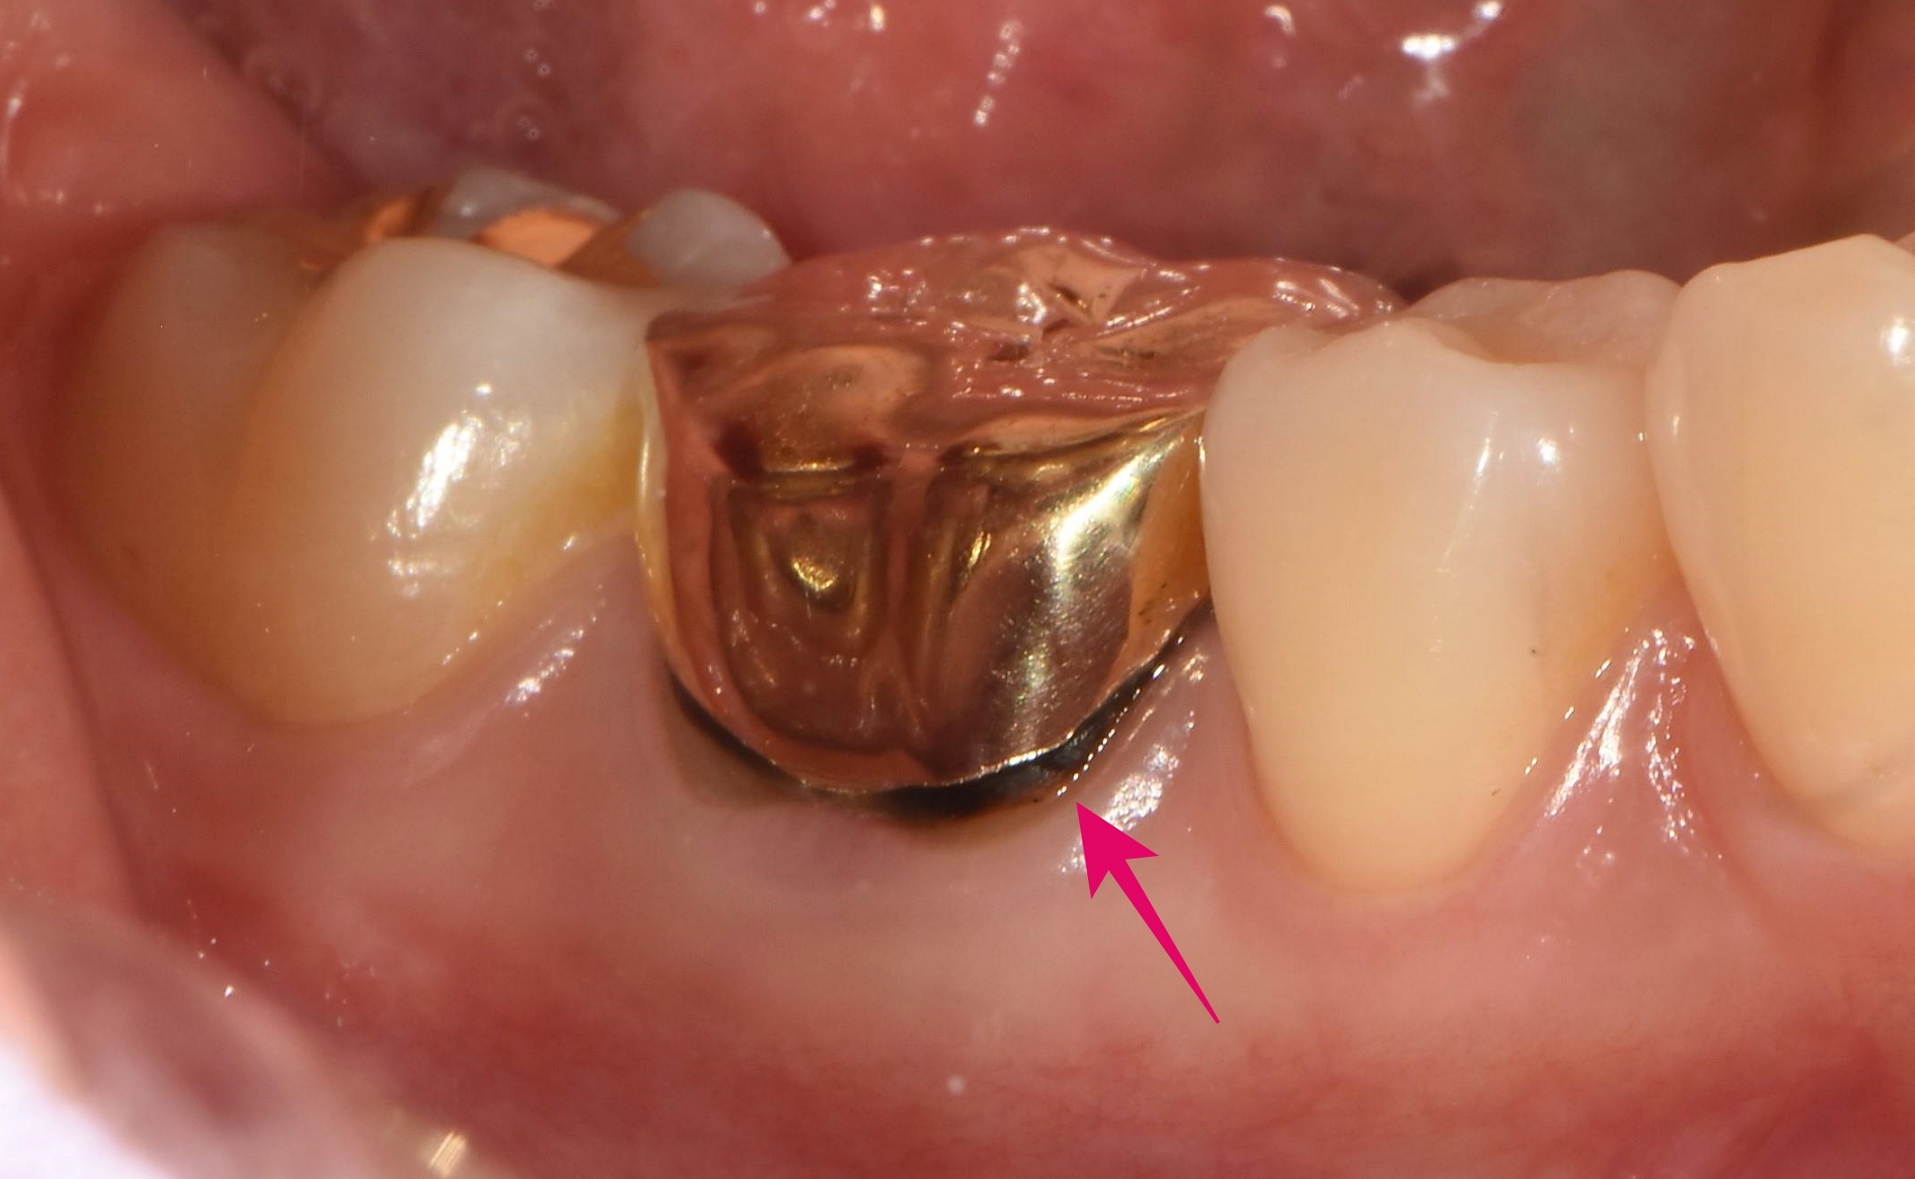

▲ 육안으로 볼 때는 구멍 난 곳 없이 튼튼해 보이는 오래된 금니

위 사진을 보시면 씹는 면은 구멍 난 곳 없이 꽤 튼튼해 보입니다. 하지만 전문가의 눈으로 세밀하게 관찰했을 때, 금니와 잇몸 경계 부위에서 미세한 이상 신호가 감지되었습니다. 앞니와의 사이 공간 잇몸 쪽에 틈이 생기고 있는 것이 확인되었습니다.